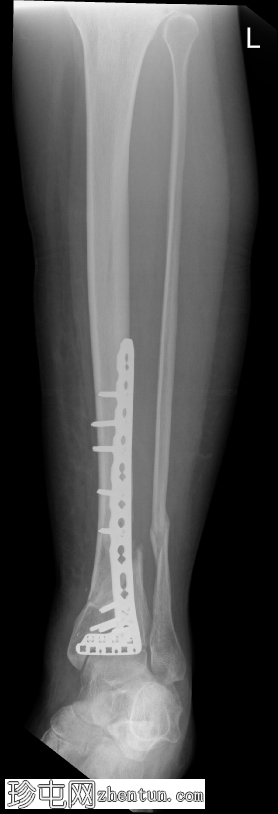

X线片

1.png

可见胫骨远端前内侧支撑钢板,并有多枚螺钉固定,与既往胫骨远端骨折切开复位内固定术(ORIF)相符。

数枚远端螺钉断裂,钢板远端与胫骨远端骨膜表面分离,提示钢板与骨骼接触不良,可能存在内固定松动或部分机械失效。其余螺钉及钢板近端部分完整,对位良好。

胫骨远端内侧可见一小块骨化良好的骨碎片,密度与邻近骨皮质相似,提示为既往骨折残留碎片,而非急性骨折碎片。

骨折部位显示部分愈合,胫骨和腓骨整体对位良好。踝关节间隙保持正常。未发现新的骨折、脱位或骨膜反应。

无既往X线片可供对比。